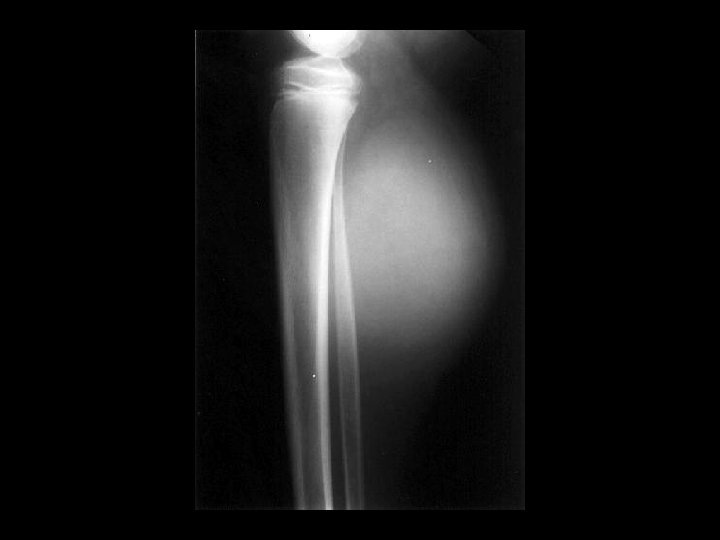

Melorheostosis • • • Findings: – Peripheral hyperostosis of the tibia producing a wavy sclerotic diaphyseal contour Rare bone disorder of childhood “candle wax” dripping down the bone appearance presents with PAIN and joint swelling ddx: – Paget’s – myelofibrosis – renal osteodystrophy – sclerotic mets